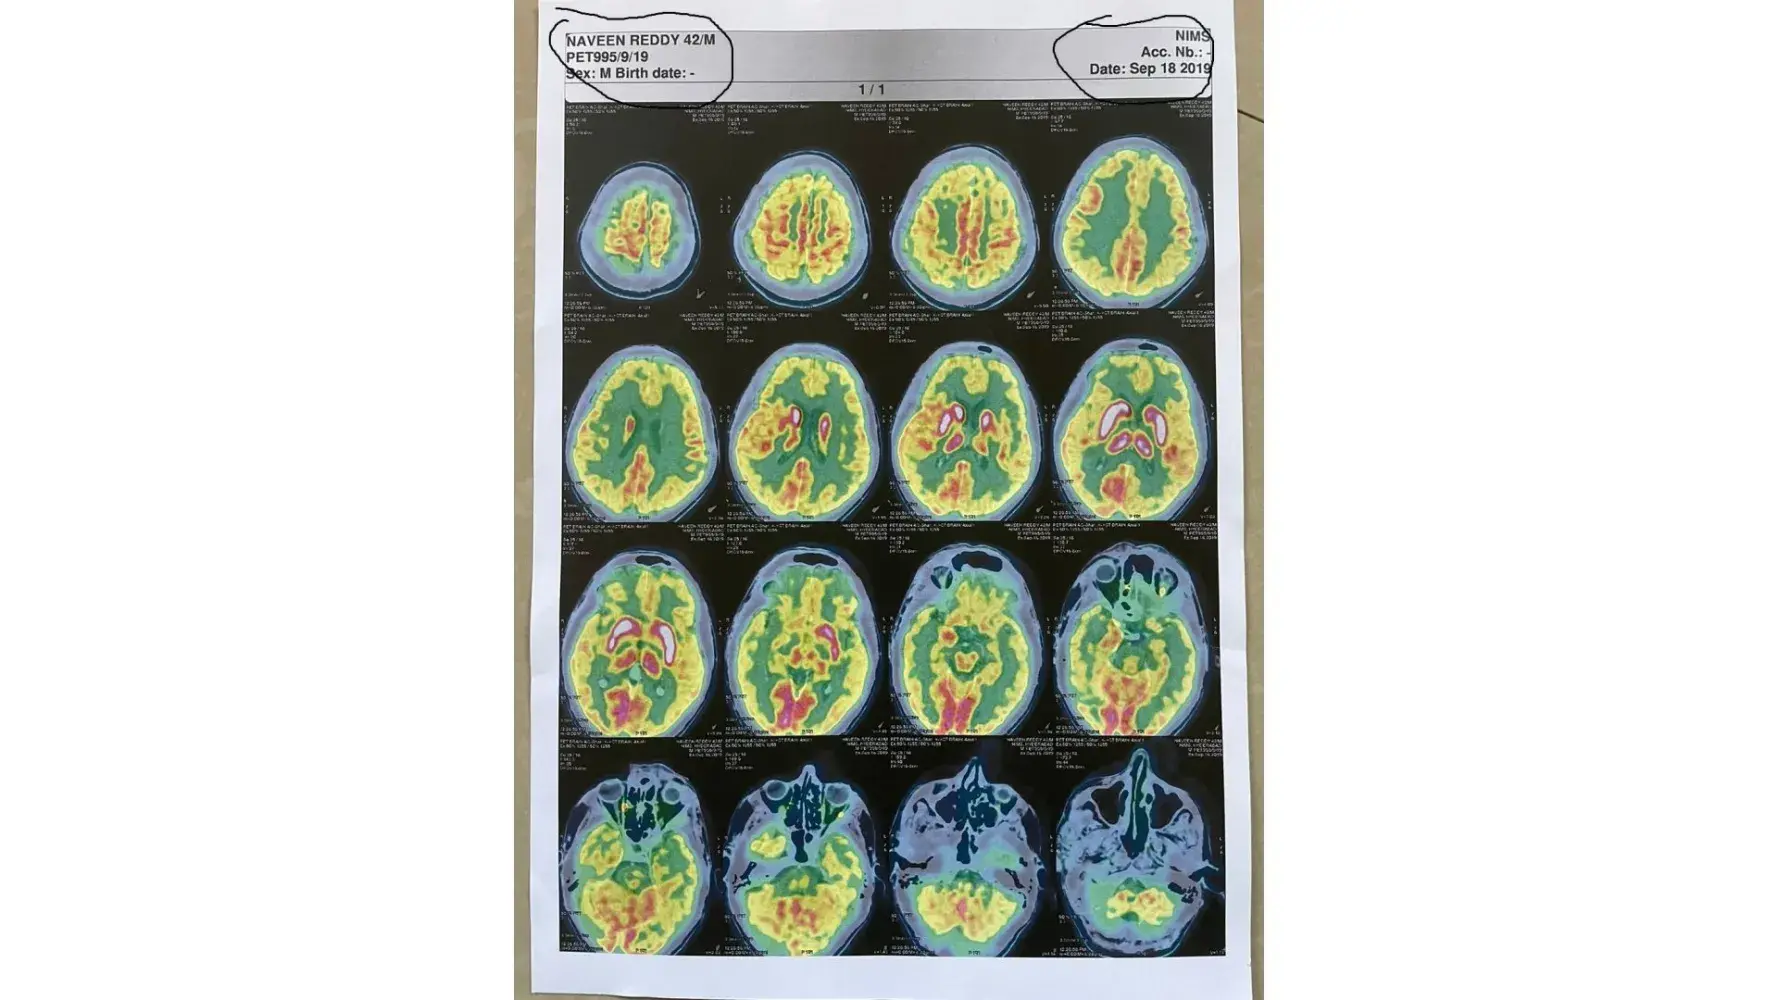

Sad part of NIMS is, behavior of staff and nurses was very rude towards patients. we recently visited to nuclear medicine for PET-CT brain scan. they showed us hell to get this done. Finally after 5 days it is done but wrong report shared to patient and requested to staff same but their response is very rude and started shouting on us.